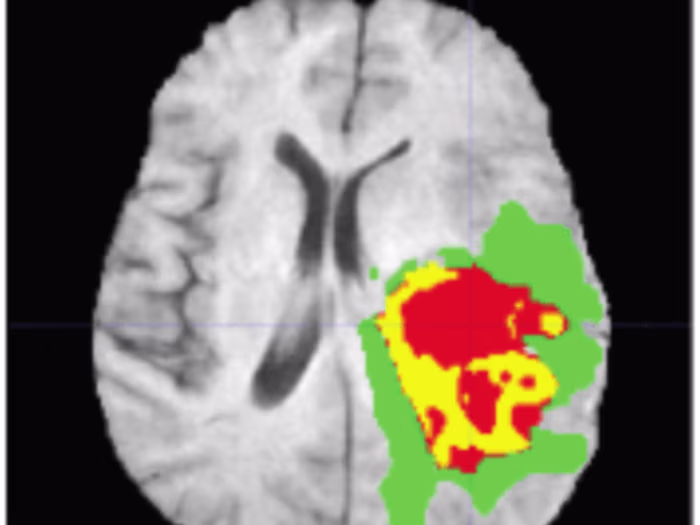

Brain Tumor Segmentation Using U-Nets